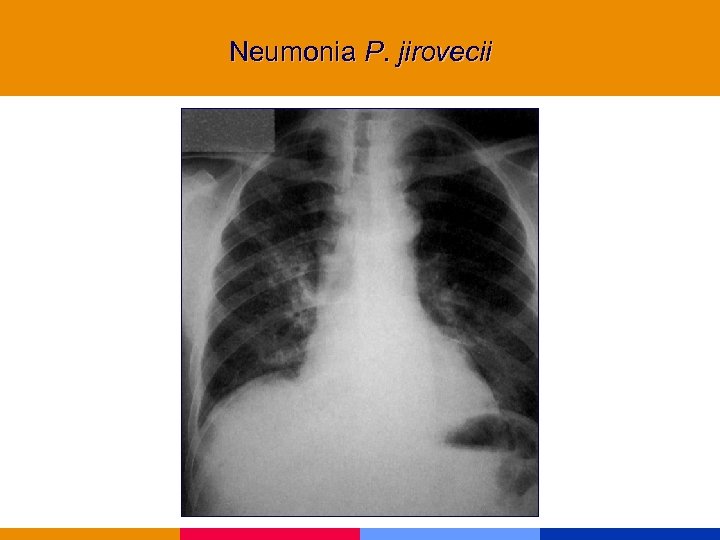

Neumonía por Pneumocistis jirovecii

Neumonía por Pneumocistis jirovecii

Neumonía por Pneumocistis jirovecii § CD 4 < 200 mm 3 § Comienzo insidioso: fiebre, tos seca, disnea. Hallazgos al examen físico incaracterísticos. § Lab: VSG: 50 mm. LDH, valor diagnóstico y pronóstico. Hipoxemia. § Rx infiltrado intersticial difuso, neumatocele, neumotórax. § TC de alta resolución.

Neumonía por Pneumocistis jirovecii § CD 4 < 200 mm 3 § Comienzo insidioso: fiebre, tos seca, disnea. Hallazgos al examen físico incaracterísticos. § Lab: VSG: 50 mm. LDH, valor diagnóstico y pronóstico. Hipoxemia. § Rx infiltrado intersticial difuso, neumatocele, neumotórax. § TC de alta resolución.

Neumonia P. jirovecii

Neumonia P. jirovecii

Neumonia P. jirovecii

Neumonia P. jirovecii

Neumonia P. jirovecii

Neumonia P. jirovecii

Neumonia P. jirovecii

Neumonia P. jirovecii

Neumonia P. jirovecii

Neumonia P. jirovecii

Neumonia P. jirovecii

Neumonia P. jirovecii

Neumonia P. jirovecii

Neumonia P. jirovecii